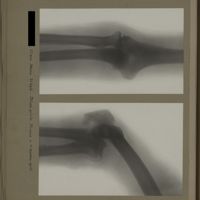

0134 - Page 22 - [Radiographies du coude et du tiers supérieur de l'avant-bras]0134 - Page 22 - [Radiographies du coude et du tiers supérieur de l'avant-bras]

0139 - Page 27 - [Radiographies du coude]0139 - Page 27 - [Radiographies du coude]

0153 - Page 41 - [Radiographies du coude]0153 - Page 41 - [Radiographies du coude]

0175 - Page 63 - [Radiographies du coude]0175 - Page 63 - [Radiographies du coude]

0187 - Page 75 - [Radiographie du coude]0187 - Page 75 - [Radiographie du coude]

0198 - Page 86 - [Radiographies du coude et de l'avant-bras]0198 - Page 86 - [Radiographies du coude et de l'avant-bras]

0201 - Page 89 - [Radiographies du coude]0201 - Page 89 - [Radiographies du coude]